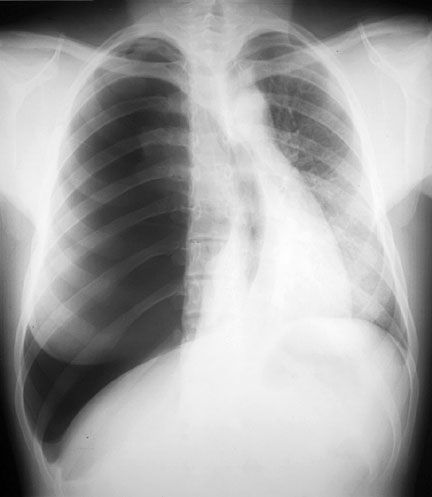

Cardiac Tamponade

- Chest x-ray: Cardiomegaly, clear lungs (may be normal)

- ECG: Low amplitude of QRS, electrical alternans